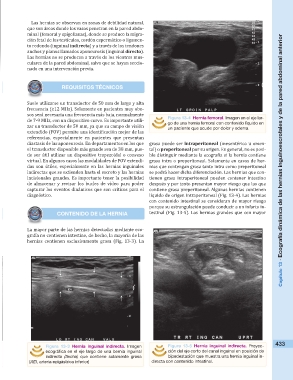

Suele utilizarse un transductor de 50 mm de largo y alta Figura 13-4 Hernia femoral. Imagen en el eje lar-

frecuencia (≥12 MHz). Solamente en pacientes muy obe- go de una hernia femoral con contenido líquido en

sos será necesaria una frecuencia más baja, normalmente un paciente que acude por dolor y edema.

incisionales grandes. Es importante tener la posibilidad líquido de origen intraperitoneal (Fig. 13-4). Las hernias

Figura 13-3 Hernia inguinal indirecta. Imagen Figura 13-5 Hernia inguinal indirecta. Proyec- 433

ecográfica en el eje largo de una bernia inguinal ción del eje corto del canal inguinal en posición de

indirecta (flecha) que contiene solamente grasa bipedestación que muestra una hernia inguinal in-

(AEI, arteria epigástrica inferior) directa con contenido intestinal.